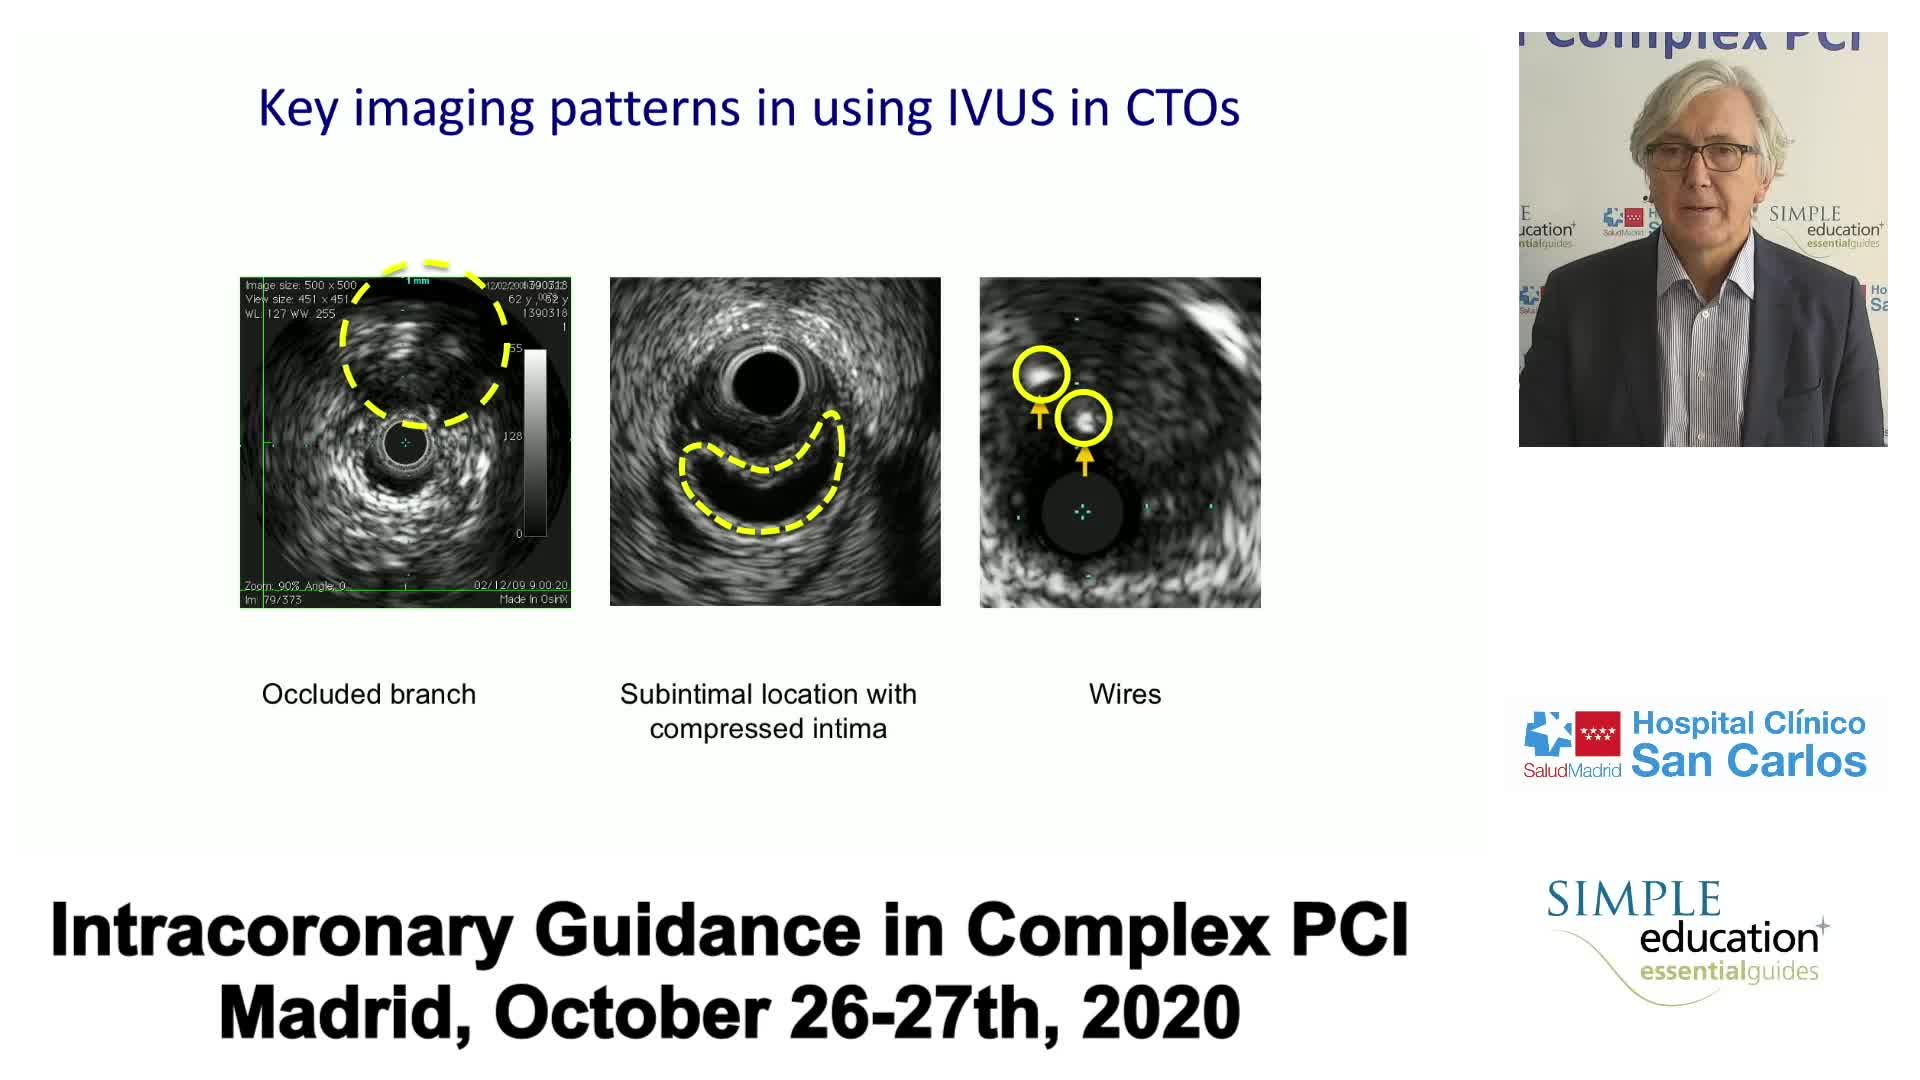

Complex PCI eCourse Madrid 26th October 2020

Complex PCI eCourse Madrid 27th October 2020

Complex PCI eCourse Madrid Day Two

Advanced PCI Course Content

Best practices and personalised medicine in complex PCI - Prof Javier Escaned